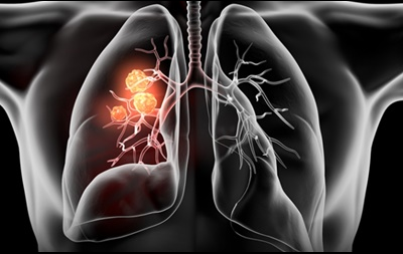

6. 폐암 초기 증상 - 혈담

혈전은 반드시 폐암이 아니어도 나타날 수 있습니다 . 혈담이란 기침 후에 피가 나오 거나 가래에 피가 섞여 있는 것을 혈담 이라고 합니다 . 그러나, 의심스러운 폐암의 초기 증상의 혈담은, 선홍색의 비교적 선명한 피가 나오는 것을 의심해 봐야 합니다 . 이것은 암세포 때문에 폐가 괴사하기 때문 입니다 . 이 경우 폐암 초기보다는 암세포가 확장되었다고 보는 것이 좋습니다 . 폐암 환자의 25% 가 혈담을 했다고 통계가 나온 적이 있습니다 .